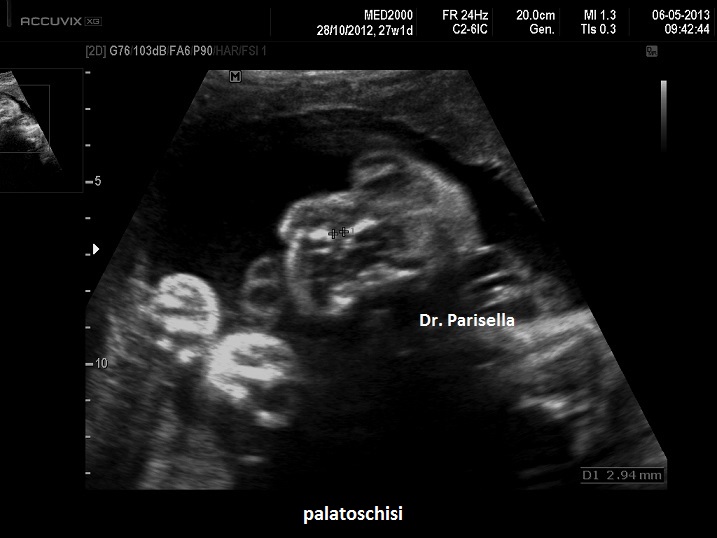

palatoschisi

Si manifesta con severa micromelia, ipoplasia toracica, piede torto, palatoschisi, micrognazia, pollici ed alluci addotti, scoliosi.